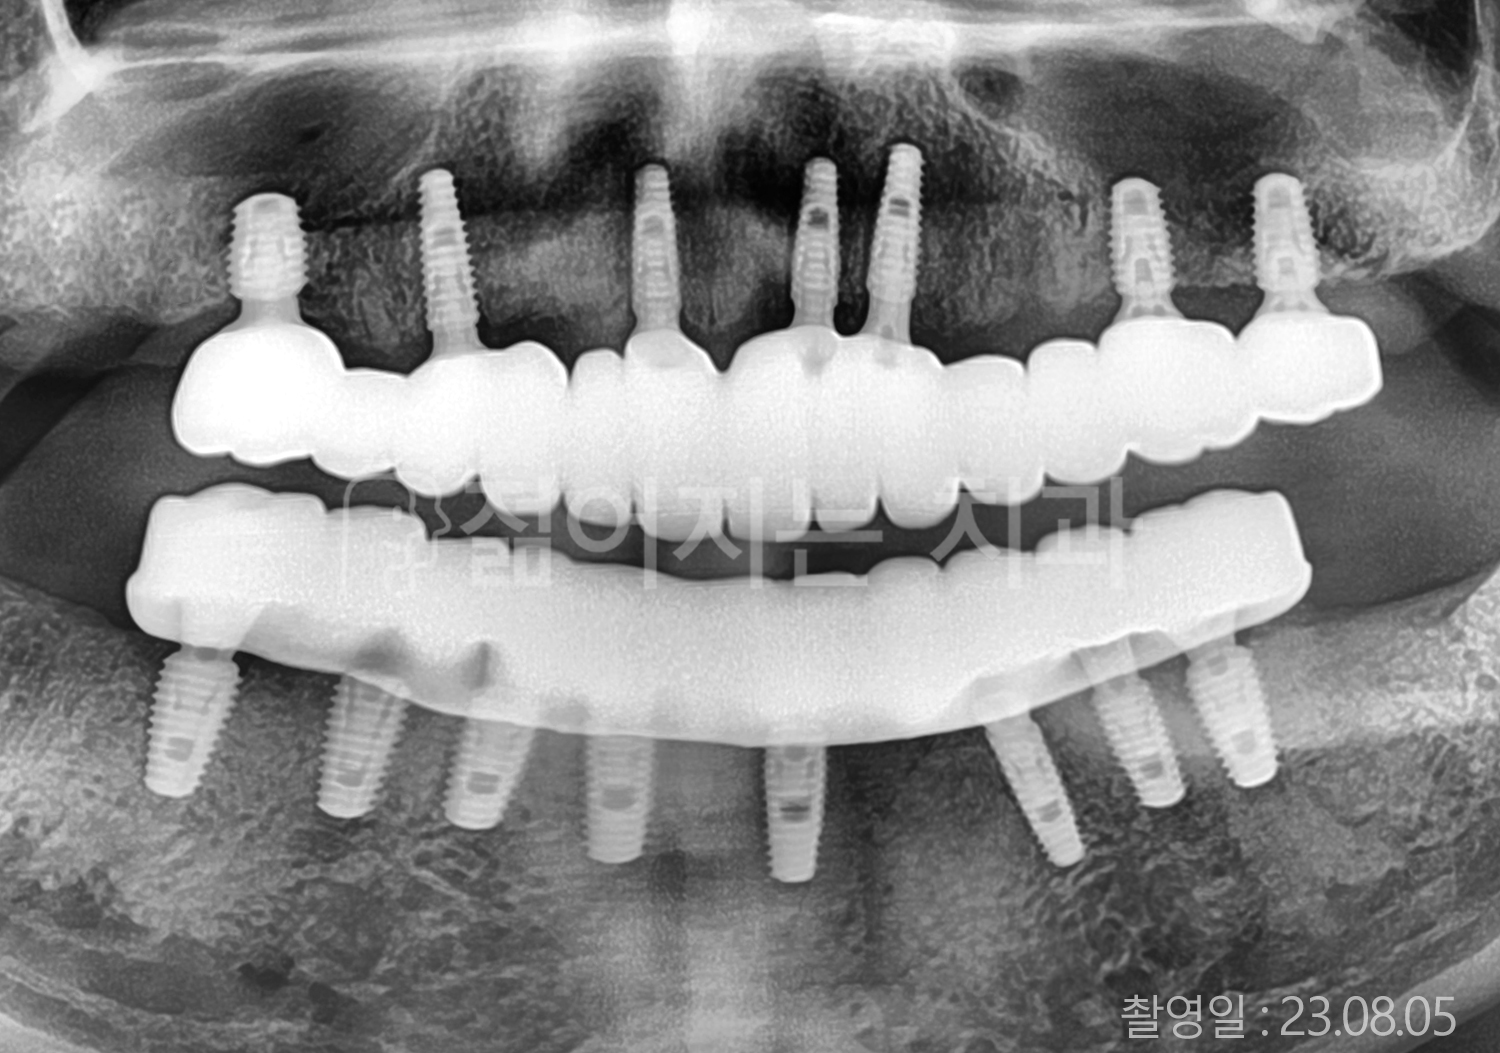

• 50대 전체치아 10개 이상 임플란트